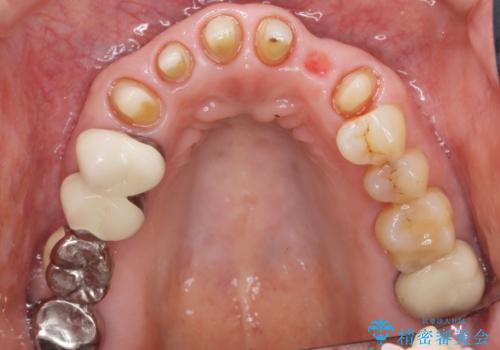

- 20年前に美容外科クリニックで治療した前歯をやりかえたいとのご希望で来院されました。

上の前歯6本はメタルボンドクラウン(内側が金属の被せ物)で補綴されており、顕著な歯肉退縮を認めました。

被せ物を除去したところ根管治療後の処置が不十分であったため、ファイバーコア(金属を用いない強くてしなやか材質の土台)を植立したのち、ジルコニアセラミッククラウンによる治療を行いました。